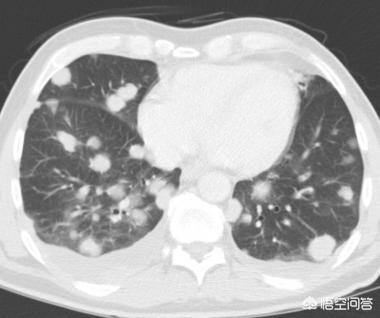

Nach weiteren 1 Jahr und 2 Monaten, die dritte Überprüfung im Dezember 2017.Sie können sehen, dass dieser Knoten ist viel größer als zuvor, die bösartigen Zeichen sind lobulierte aus und es hat sich im Inneren fest, diese Zeichen diagnostizieren die Lunge Krebs im Grunde, aber der Patient immer noch nicht haben Chirurgie.

Nach einem weiteren Jahr, bei der vierten Untersuchung im Januar 2019, hatte sich der Knoten in eine Masse (>3 cm) verwandelt, und dieses Lungenkarzinom war lehrbuchmäßig, mit im Grunde allen Anzeichen einer Bösartigkeit, die für Lungenkrebs sprechen.Unregelmäßige Ränder, Läppchen, Grate und Anzeichen von Pleuraziehen.